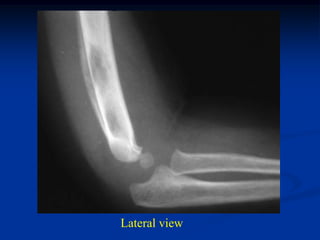

Case #1097

14 year male with

adamantinoma distal

tibia and fibula